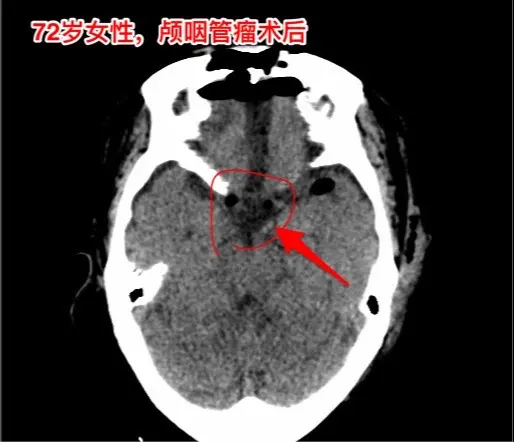

颅咽管瘤不单单是小孩子得的病!很多人认为颅咽管瘤是小孩子得的病,其实各个年龄段的人都可以患颅咽管瘤,我见过的颅咽管瘤病人年龄跨度从不到一岁到八十多岁! 相对而言,小孩子群体中(小于15岁)颅咽管瘤的发生率比较高! 这个72岁的山西晋城市老人在古稀之年患上了颅咽管瘤,病理报告是乳头型颅咽管瘤。10月25日在我科作了手术,11月13日出院。 老人在住院前胃肠功能不好,经常腹胀、消化不良。手术后也是经常感觉腹胀、食欲不振,身体康复过程相对比较缓慢。 老年人一般来说都伴有老年性疾病,比如糖尿病、高血压病、高脂血症、动脉硬化,身体大脏器机能下降,所以老年人患颅咽管瘤,作手术后恢复会比较慢,出意外的风险会增加,尤其是血管方面的并发症会增加,比如深静脉血栓、心肌梗死等。